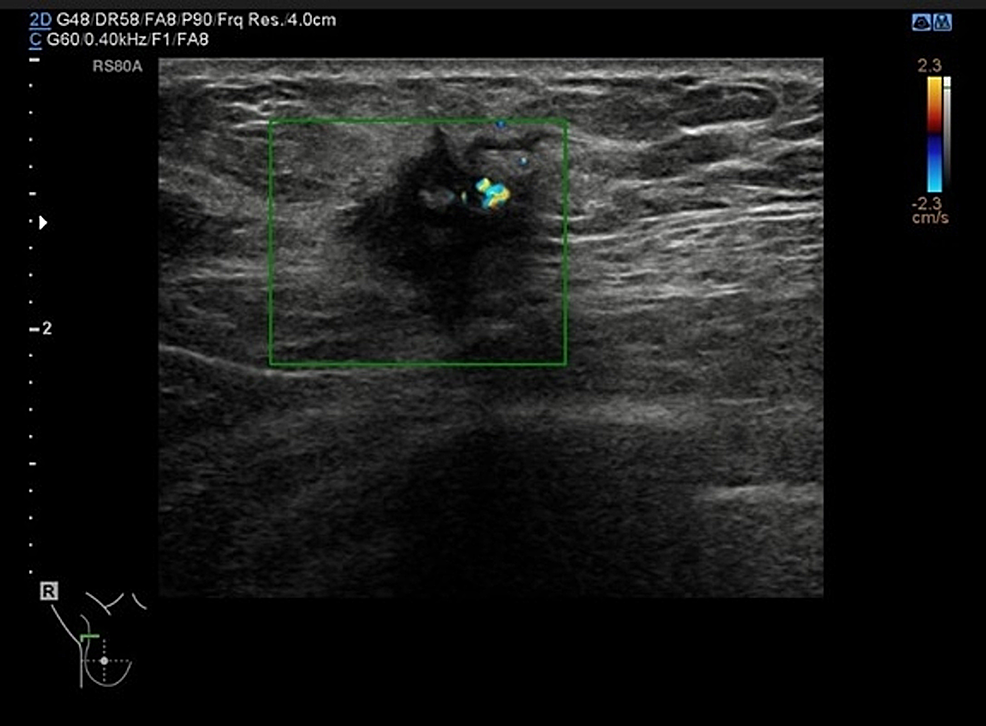

Mammogram (Figure 1) showed a 25-mm suspicious lesion in the right axillary tail, which was also visualized on ultrasound (Figure 2), along with a suspicious lymph node in the right axilla. Imaging-guided core biopsies were taken from both; the histopathology was consistent with grade 1 invasive ductal carcinoma, and ER 0, PR 0, and HER 2 negative as well. Mastectomy with axillary clearance was performed after consultation with breast MDT (multidisciplinary team). The post-operative histopathology revealed 23-mm, grade I, triple-negative invasive ductal carcinoma (Figure 3) with lymphovascular invasion, Ki67 10%, one out of nine lymph nodes showing metastatic disease, and the final staging as T2N1M0. The MDT advised for annual surveillance for five years.